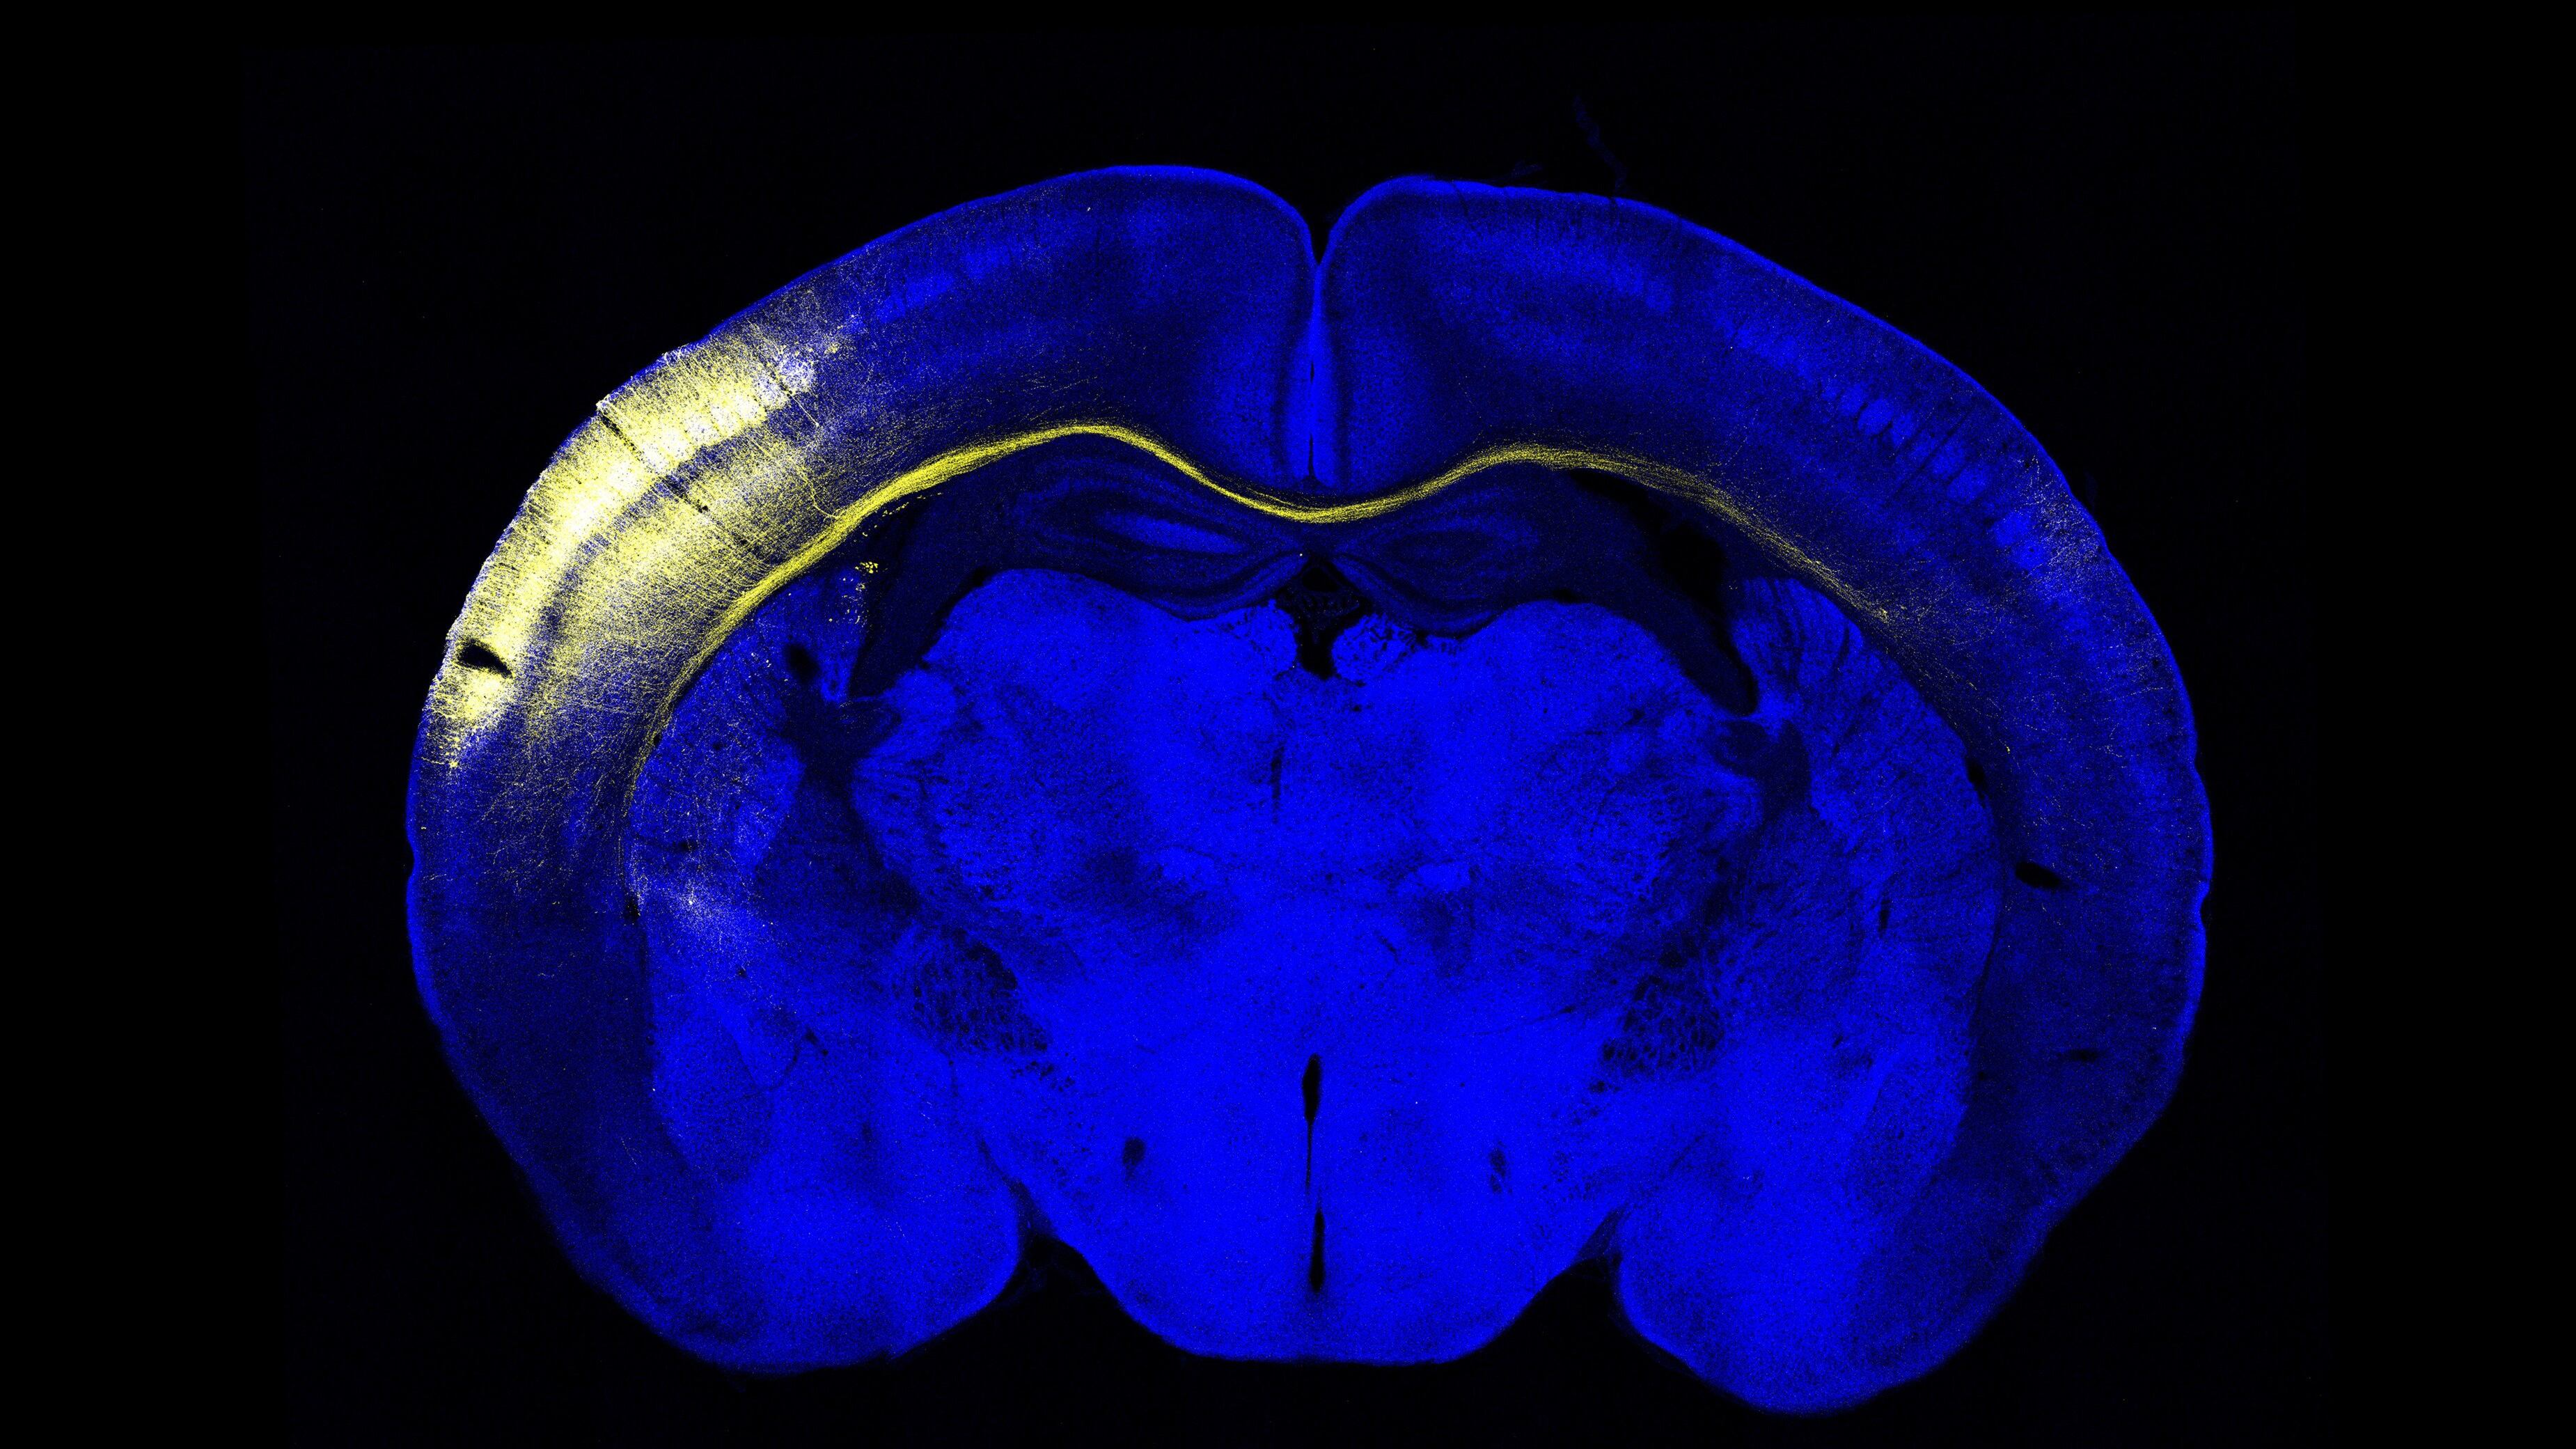

En este trabajo, cuyo primer autor es Roberto Montanari, han conseguido describir de forma precisa el circuito completo que comunica ambos hemisferios cerebrales: la información percibida ante un estímulo sensorial viaja a través del cuerpo calloso y es procesada específicamente en una región muy concreta de la corteza somatosensorial primaria, en el ratón los barriles de la fila A (RowA).

Por lo tanto, estos representan un centro sensorial para la comunicación interhemisférica. Además, han comprobado que la información viaja a través de un carril concreto. La corteza cerebral que codifica la información táctil del ratón se divide en filas y columnas y cada una de ellas contiene grupos de neuronas que se denominan "barriles".

Los investigadores han comprobado que la comunicación entre hemisferios se produce en la fila A: "Es lo que se llama proyección heterotópica. Por ejemplo, los barriles de la fila E apenas proyectan a la fila E del otro hemisferio, sino que lo hacen a través de la fila A", explica el director del laboratorio de Procesamiento sensorio-motor en áreas subcorticales del IN Ramón Reig, y añade que esto "es muy interesante porque es precisamente en la fila A donde se encuentran los receptores de los bigotes de la línea media".

Para validar estos resultados, los investigadores imitaron lo que habían llevado a cabo, a nivel sensorial, en los bigotes del ratón con técnicas de optogenética. El experimento consistió en estimular directamente con luz la corteza cerebral para observar la respuesta de las neuronas de las filas A y, efectivamente, observaron que la respuesta coincidía y daba lugar al mismo fenómeno.